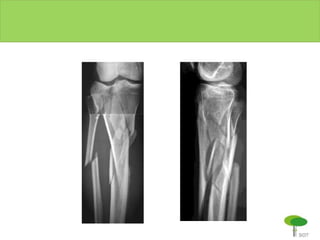

FIXADOR EXTERNO

FIXAÇÃO INTERNA C/ ESTABILIDDADE ABSOLUTA